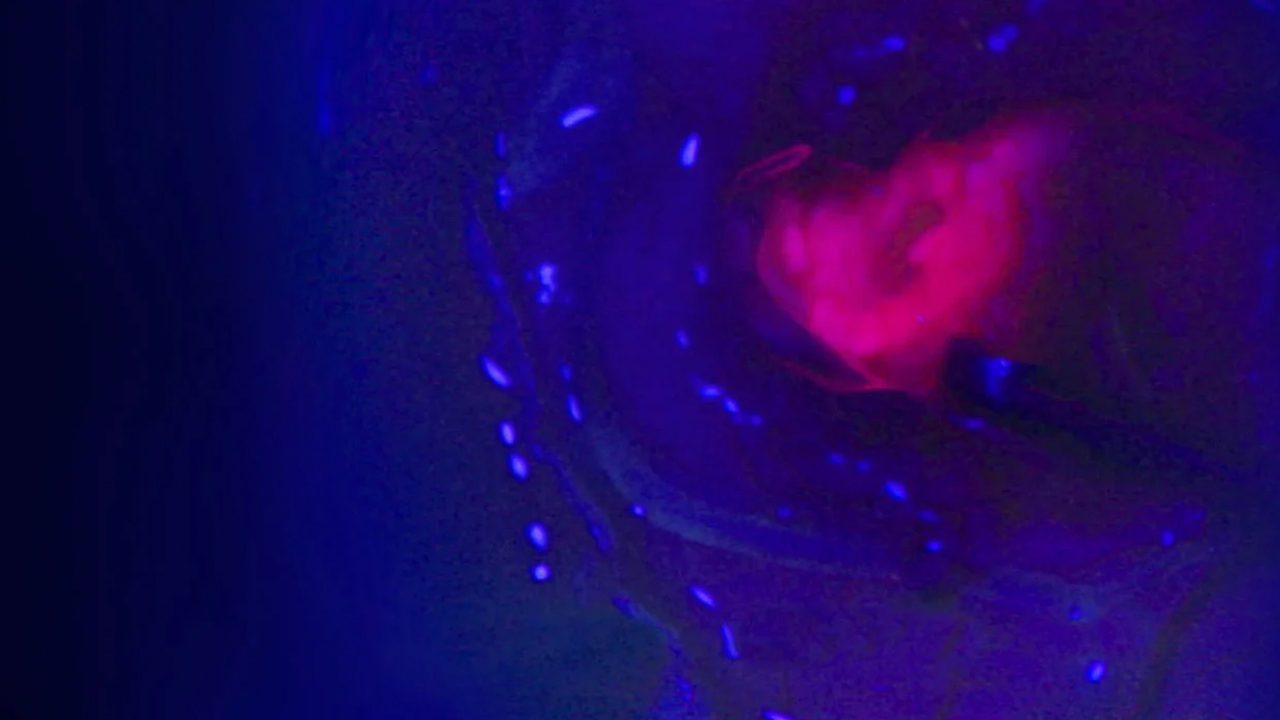

• Fluorescence Imaging

ZEISS BLUE 400 S – Fluorescence Oncology with 5-ALA

The system with 5-ALA marker, provides high-quality visualization during neurosurgery to help surgeons identify tumor tissue associated with Grade III and IV gliomas. Enhanced clarity—particularly of both fluorescent and non-fluorescent tissue—supports more accurate differentiation between tumor and healthy brain tissue. For patients, this improved visualization helps surgeons remove as much tumor as safely possible while preserving surrounding healthy tissue, supporting better surgical outcomes and neurological safety.

Fluorescence Imaging.jpg